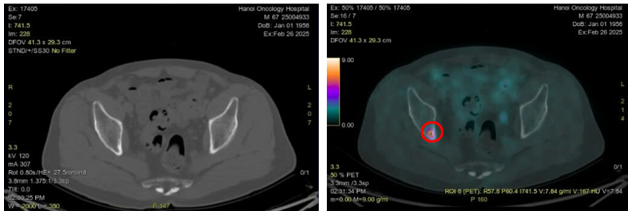

Hình 7: Hình ảnh CT cấu trúc bình thường (bên trái) và hình ảnh tăng hoạt tính phóng xạ ở xương chậu phải trên PET/CT (vòng tròn màu đỏ) (SUVmax:7,84)

-         Sau khi chụp PET/CT để đánh giá giai đoạn trước điều trị phát hiện tổn thương thứ phát tại xương ức và xương chậu phải, dù trên hình ảnh CT không phát hiện sự biến đổi về mặt cấu trúc tương ứng với vị trí các xương này. Về mặt lý thuyết sự biến đổi về mặt chức năng thường xảy ra trước khi có sự biến đổi về mặt cấu trúc với thời gian khoảng 6 tháng.

-         Việc ghi hình PET/CT giúp phát hiện và định vị chính xác vị trí tổn thương di căn từ đó giúp xác định chính xác giai đoạn bệnh. Đối với trường hợp bệnh nhân trên nếu chỉ dựa trên kết quả chụp chiếu CT đơn thuần sẽ bỏ sót các tổn thương thứ phát ở xương. Việc chụp PET/CT giúp phát hiện các tổn thương di căn tại vị trí xương ức và xương chậu dẫn tới sự thay đổi về hướng điều trị, cu thể trên bệnh nhân này không còn chỉ định phẫu thuật hay xạ trị triệt căn nữa và sẽ tiến hành điều trị toàn thân và chăm sóc giảm nhẹ.